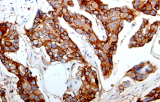

L’immunoistochimica (IHC) con anticorpi primari CE/IVD è essenziale per una diagnosi e classificazione accurata sia delle malignità ginecologiche che mammarie. Questi anticorpi consentono la rilevazione precisa di marcatori tumorali e proteine cellulari, supportando la diagnosi differenziale e guidando strategie terapeutiche personalizzate.

Studi recenti sottolineano il valore diagnostico delle proteine del complesso SWI/SNF, in particolare ARID1B, nell’identificazione di malignità ginecologiche dedifferenziate e indifferenziate – tumori aggressivi con prognosi sfavorevole. L’IHC di ARID1B offre alta specificità e viene sempre più integrata nei pannelli diagnostici per migliorare la precisione. Pannelli con marcatori aggiuntivi supportano anche la differenziazione dei sarcomi uterini, aumentando l’accuratezza diagnostica. Evidenze emergenti suggeriscono che ARID1B potrebbe rappresentare un potenziale bersaglio terapeutico nel carcinoma ovarico a cellule chiare, sebbene le applicazioni cliniche rimangano in fase di ricerca.